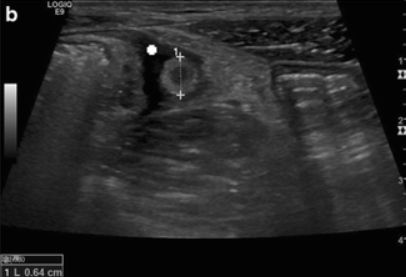

Appendicolith